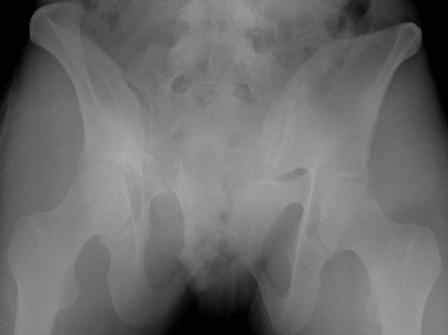

Серия до- и послеоперационных снимков этой пациентки. Хотя бы post factum обсудить. Не знаю, что можно сделать с задними отделами стержневым аппаратом, но три крепких парня открытым путем с помощью "волшебных" слов еле-еле смогли отрепонировать - сзади все было очень ригидно!